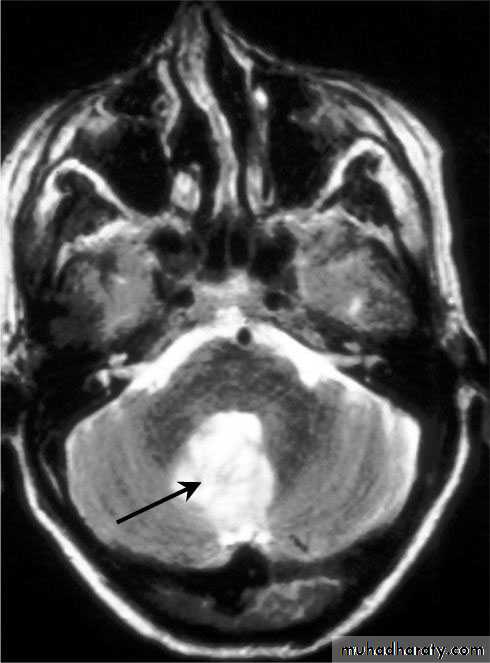

Cerebellar Abscess

Neurosurgery